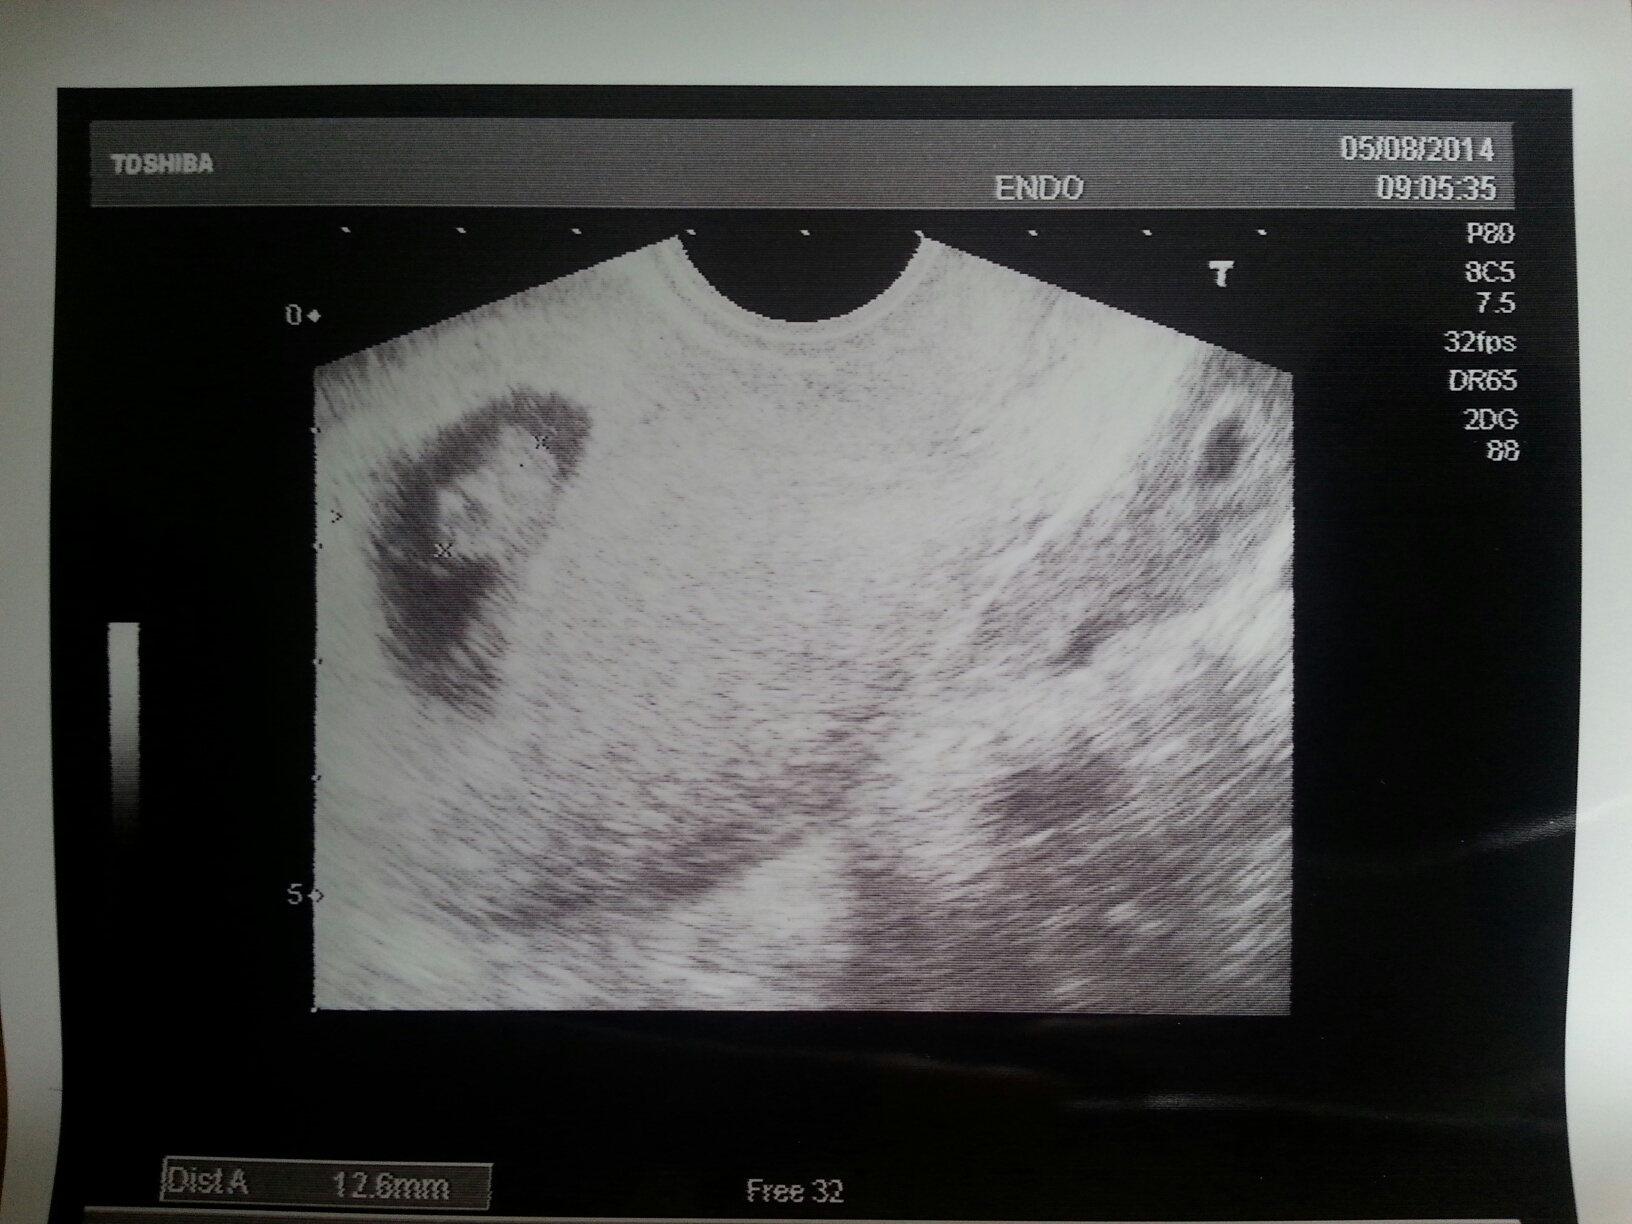

Intanto posso dirvi che, tramite tutto quel ronzio, hanno stabilito che sono gia' vecchio di 8 settimane e lungo 1.26cm.

Vedete quelle due piccole 'x'?

Sono poste alle mie estremita'. Servono per misurarmi.

Quella in basso e' proprio sulla mia testa, quella in alto e' alla fine di due estremita' che a loro volta si stanno dividendo in una serie di 5 estremita' piu' piccole... quando saro' piu' grande voglio provare a prenderle e sentire che odore e gusto hanno...